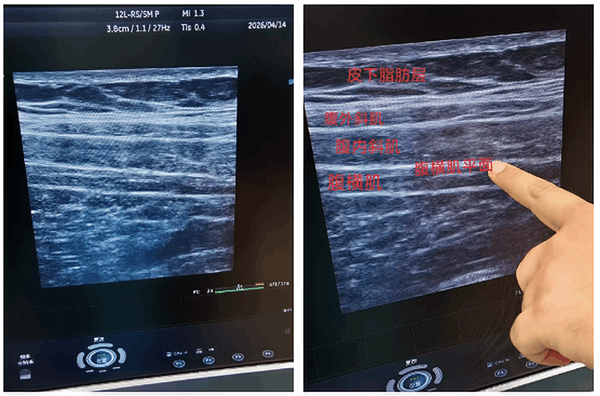

超声定位下腹横肌平面阻滞是当前腹腔镜手术围术期镇痛的前沿技术,依托高清超声诊疗设备,实现全程可视化精准操作:

麻醉医师在超声实时引导下,可清晰辨识腹壁肌肉层次、血管及神经走行,精准定位腹内斜肌与腹横肌之间的神经筋膜层,将镇痛药物精准注入目标区域,阻滞走行于此平面的腹壁神经,以达到腹壁区切口镇痛和麻醉的效果。让麻醉操作更具安全性、可控性,为腹腔镜手术患者构建坚实的镇痛安全屏障。